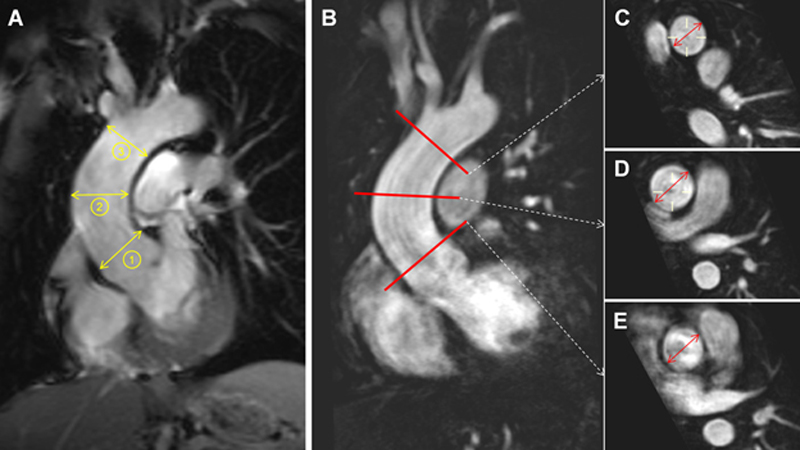

Two experienced radiologists (S.D.H. and S.D.Q.) analysed the anonymised images on a commercially available DICOM workstation (Advantage Window, GE Healthcare, Milwaukee, USA), blinded to patient’s characteristics and date of the examination. For each patient, the maximal endoluminal diameters of the ascending aorta at the sino-tubular junction (STJ), the proximal ascending aorta at the level of the right pulmonary artery (pAsAo), and of the distal ascending aorta (dAsAo) before the origin of the brachiocephalic artery were measured (fig. 1). At each level, the average diameter obtained from two measurements in two orthogonal planes was used for analysis.

Figure 1 Measurement of the aortic diameters. A. With datasets where 3-D MR-angiography was not available, the luminal diameters, at end-diastole, were directly measured on a non-cine SSFP acquisition of the ascending aorta in the coronal plane at three different levels: (1) sino-tubular junction, (2) proximal ascending and (3) distal ascending aorta. B. In all cases where MR-angiography was available the maximal diameters were measured on the individual aortic cross-section planes reconstructed at the level of the distal ascending aorta (C), proximal ascending aorta (D) and sino-tubular junction (E)